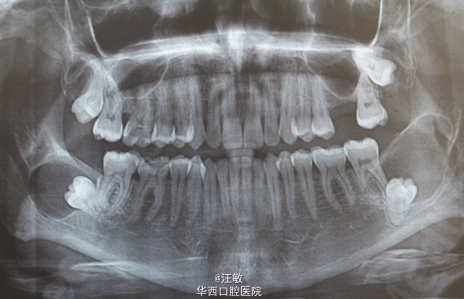

病人24岁,因右下第一磨牙出现牙髓炎症状就诊,拍摄全景片时意外发现双侧下颌第三磨牙周围被透亮阻射线包围。患者没有出现任何症状,根据临床和影响初步判断为牙源性囊肿,尤其是含牙囊肿,成釉细胞瘤和牙源性角化囊肿,因此没有做抽吸活检。